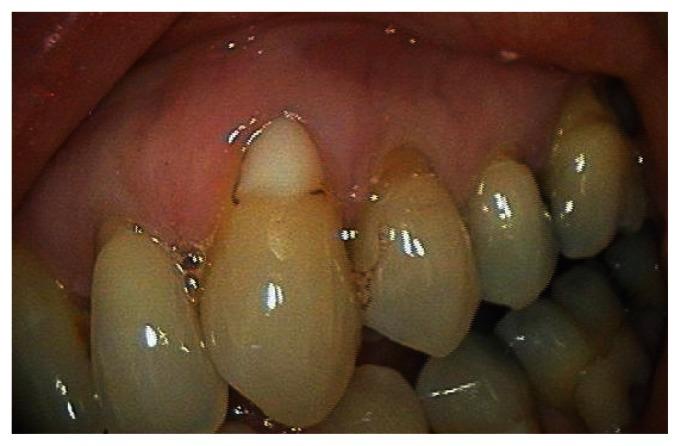

This case report describes the treatment of a maxillary canine that had 4 mm of marginal gingival recession. The exposed root had been previously restored with a composite class 5 restoration. The restoration was removed and the root planed and demineralized. The root was then covered by a subepithelial connective tissue graft harvested from the palate. The flap was coronally positioned to completely cover the graft and exposed root. The healing was photographed post-operatively at one month, six months, and seven years. Root coverage increased to 100% after seven years. The zone of attached gingiva also increased.